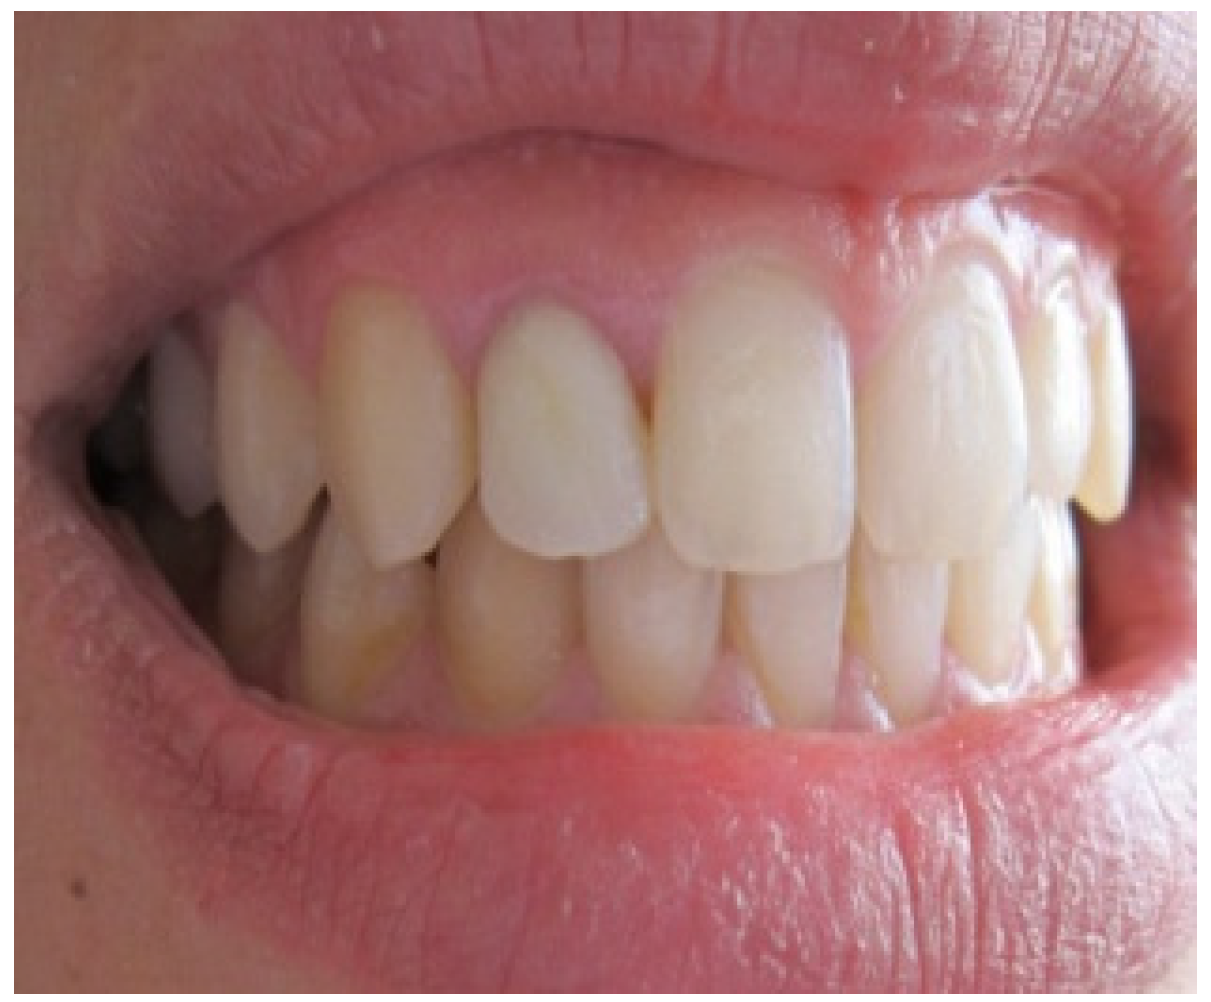

Aesthetic assessment showed a squared teeth form, a size discrepancy and a non-symmetrical gingival architecture between the left and right lateral incisors (Figure 2). A slight asymmetry between the gingival margins of the right and left central incisors was noticeable. However, the patient did not express her dissatisfaction about it and refused any surgery on her sound teeth.

Figure 2. Gingival display due to the asymmetrical ZENITH.